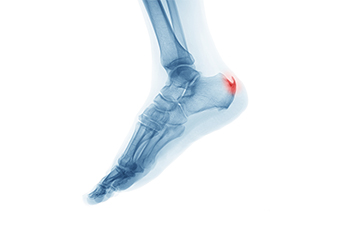

It is possible to have a heel spur without showing signs of any symptoms. However, if inflammation develops at the point of the spur’s formation, you may have pain while walking or running. In terms of diagnosis, sometimes all a doctor needs to know is that the patient is experiencing a sharp pain localized to the heel to diagnose a heel spur. Other times, an x-ray may be needed to confirm the presence of a heel spur.